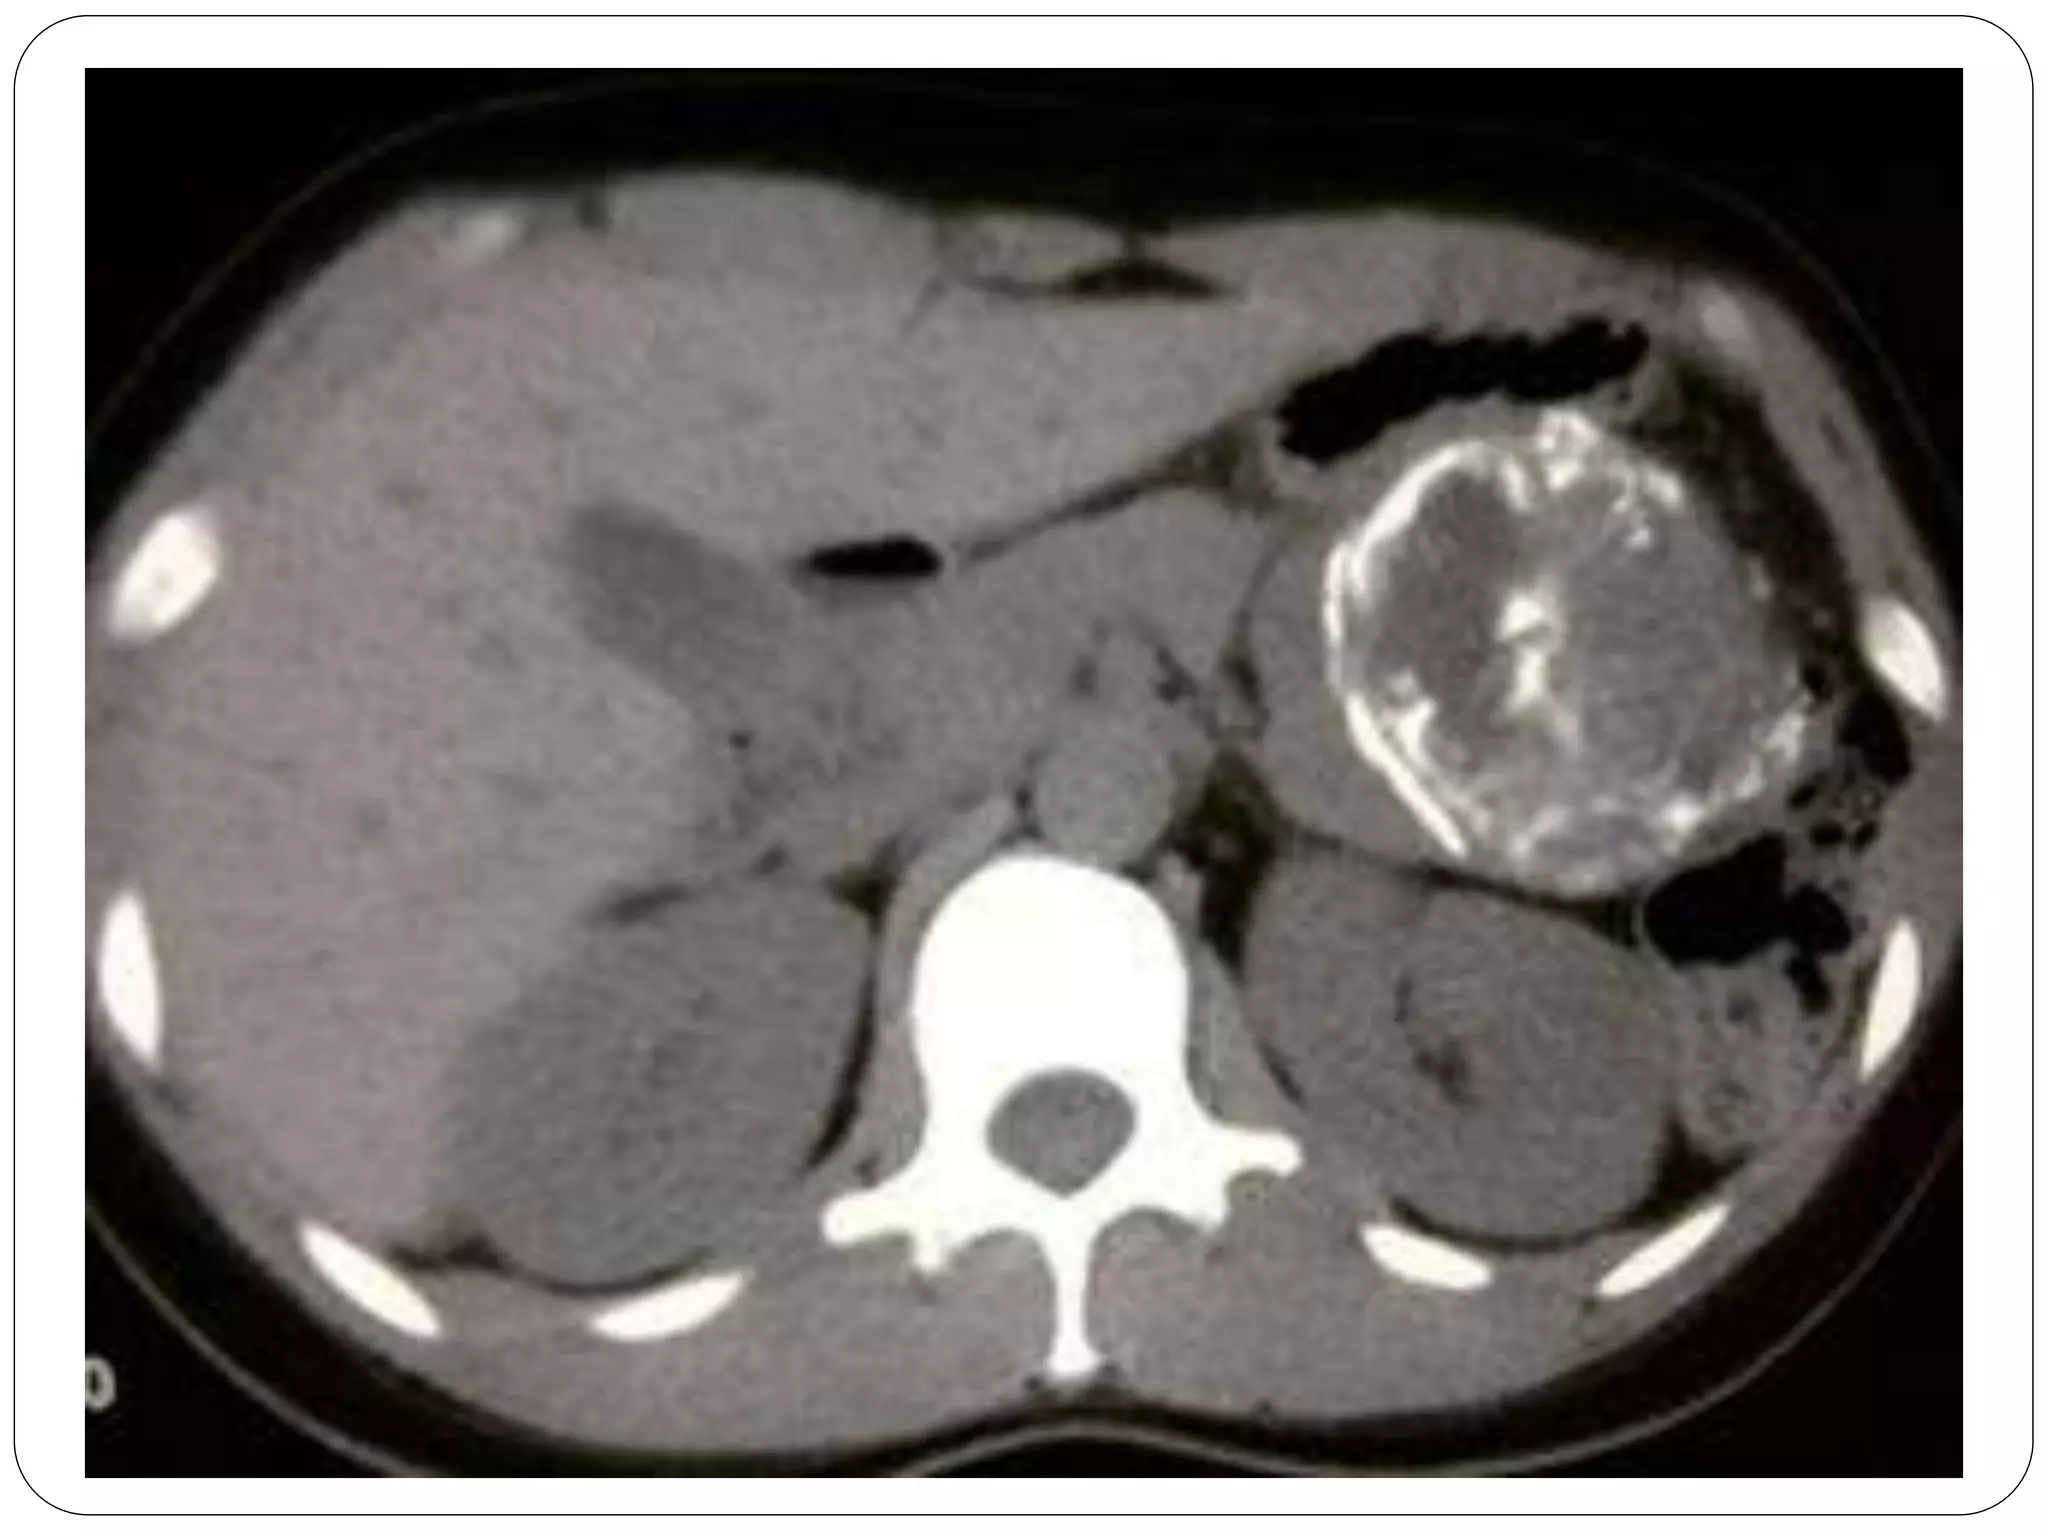

• #5 Well-circumscribed neoplasm with solid and cystic components Calcifications in ~ 30%

• #6 Well-circumscribed neoplasm with solid and cystic components Calcifications in ~ 30%